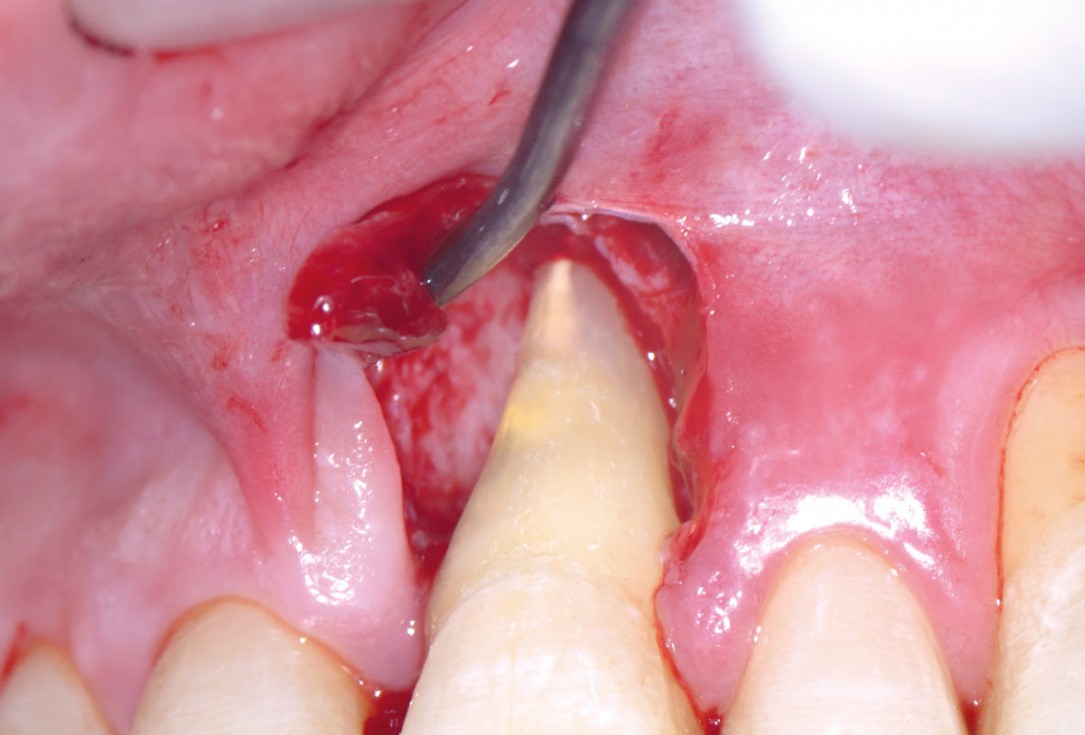

04/11 - Access to the defect using EPP technique by avoiding an incision over the defect-associated papilla. Note: the osseous defect involving the apexEntire papilla preservation technique (EPP) for the regenerative treatment of a severely compromised central incisor - Dr. S. Aslan